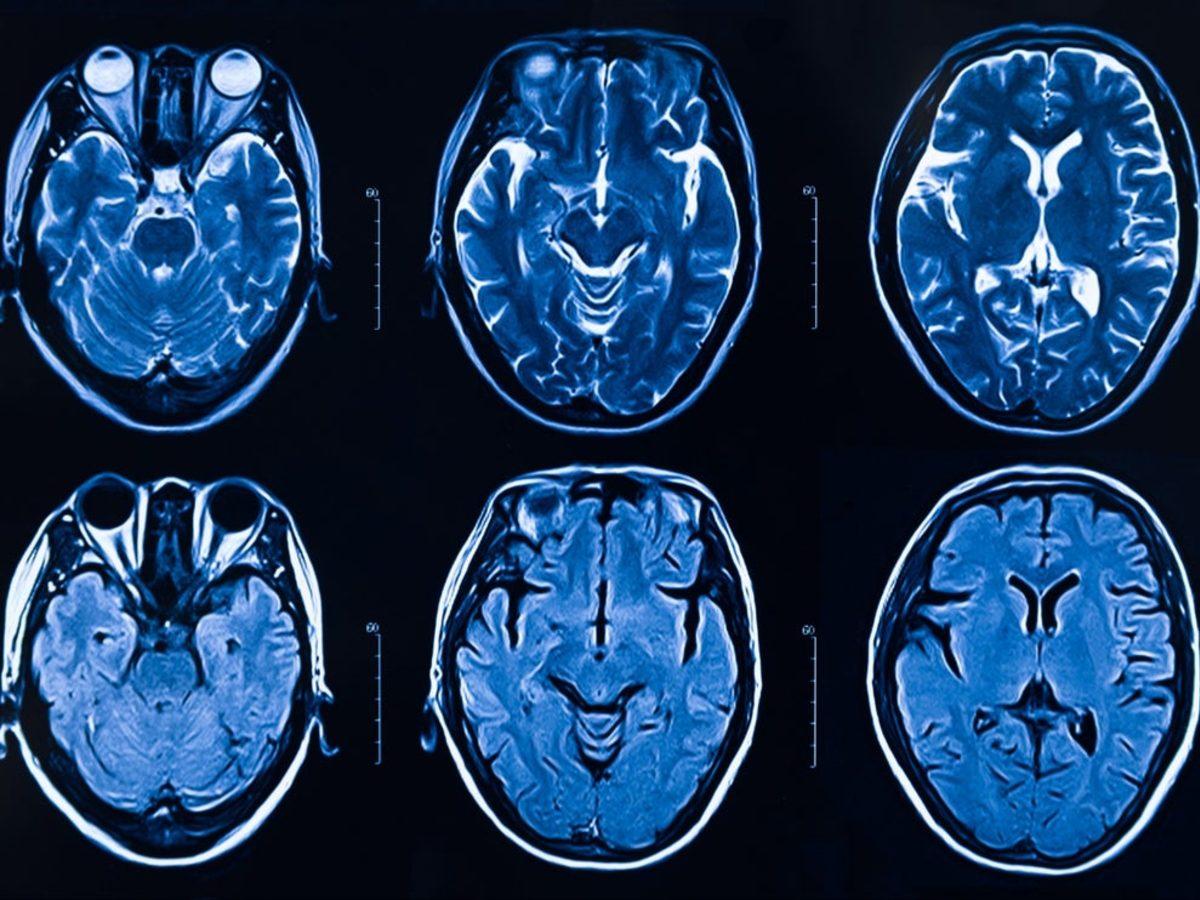

Şu an için koronavirüsün beyne nasıl ulaştığı ve nasıl bir etki gösterdiği bilinmiyor. Ancak bazı COVID-19 hastalarının baş ağrısı, kafa karışıklığı ve deliryum gibi nörolojik semptomlar göstermesi, koronavirüsün beyni enfekte edebileceğini ortaya koyuyordu. Bilim insanlarına göre vakaların genetik mirasları ya da yüksek viral duyarlılıkları, koronavirüsün beyni enfekte edebilmesine yol açıyor.

Yale Üniversitesi'nden immünolog Akiko Iwasaki liderliğinde gerçekleştirilen çalışma; COVID-19 nedeniyle hayatını kaybeden birinin beyin dokusunda, bir fare deneyinde ve beyni üç boyutlu olarak taklit etmek için laboratuvarda bir araya getirilen beyin hücresi kümelerinde (Organoid) virüs tespit ederek beynin enfekte olabildiğini belgelemiş durumda.

Çalışmaya göre koronavirüs, beyne enfekte olduktan sonra diğer beyin hücrelerine doğru yayılıyor ve nöronların diğer beyin hücreleriyle iletişim kurmasını sağlayan sinapsların sayısını hızla azaltıyor. Daha da önemlisi virüs, komşu hücrelere oksijen gitmesini engelleyerek beyin hücrelerinin ölmesine neden oluyor.